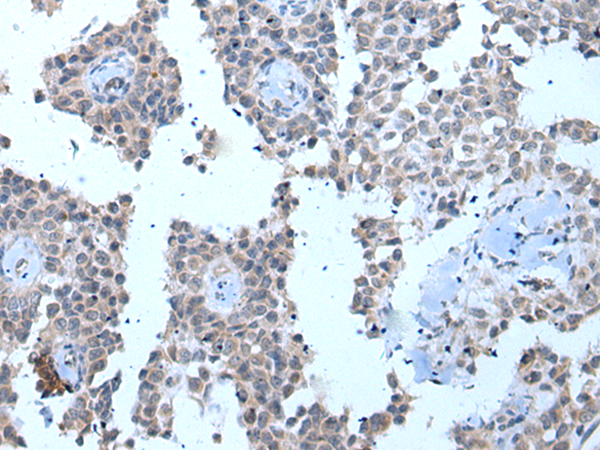

分类: 科研抗体货号: P12843别名: NLZ1; ZPO1; ZEPPO1; ZNF503L应用: IHC反应种属: Human, Mouse